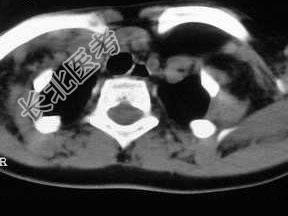

- 单项选择题女,17岁, 发现左侧颈部包块半年余,PE: 病灶质软,境界不清, 无压痛,CT如图所示, 最可能的诊断是 ( )

D、颈部淋巴管瘤